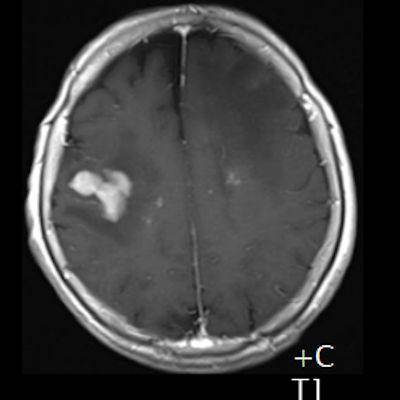

- (B) Aksiyel postkontrast T1A görüntülerde büyüğü sol frontalde kontrastlanma gösteren multipl kitle lezyonları (oklar) izlenmektedir.

- Olguda tanı sol frontalde kontrast tutan lezyondan yapılan beyin biyopsisi ile konulmuştur.

- Genellikle supratentoriyal alanda, bazal ganglion, periventriküler beyaz cevher, orta hat ve korpus kallozum vb. yerleşme eğiliminde tek veya multipl kitleler şeklinde görülür.

- Kitleler çoğunlukla solid ve homojendir.